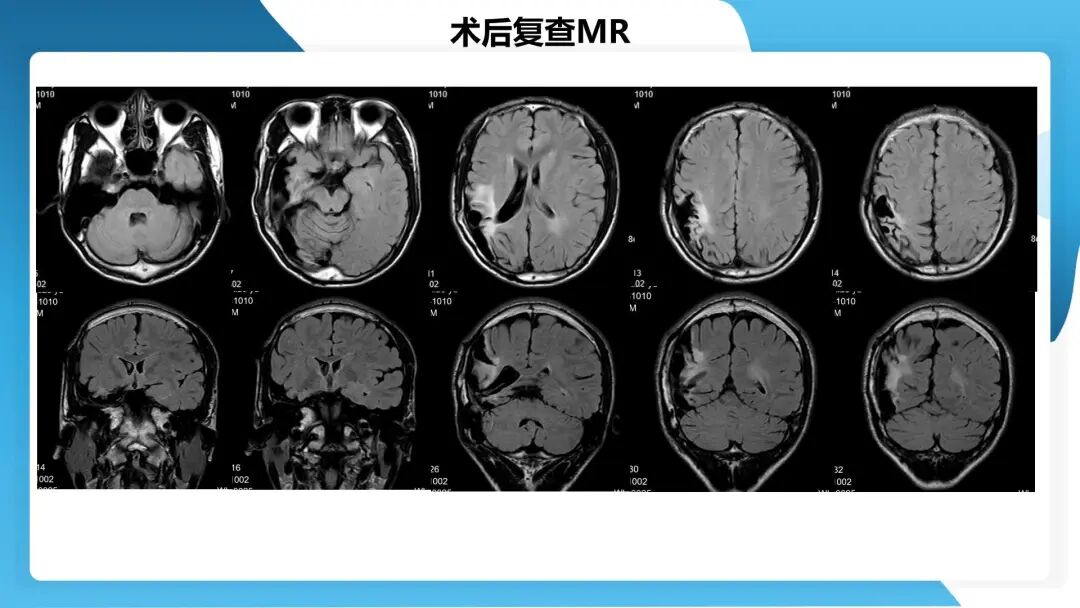

《「痫停」信步》癫痫治疗病例荟萃第四十四期---颞前叶及脑软化灶切除治疗难治性癫痫一例